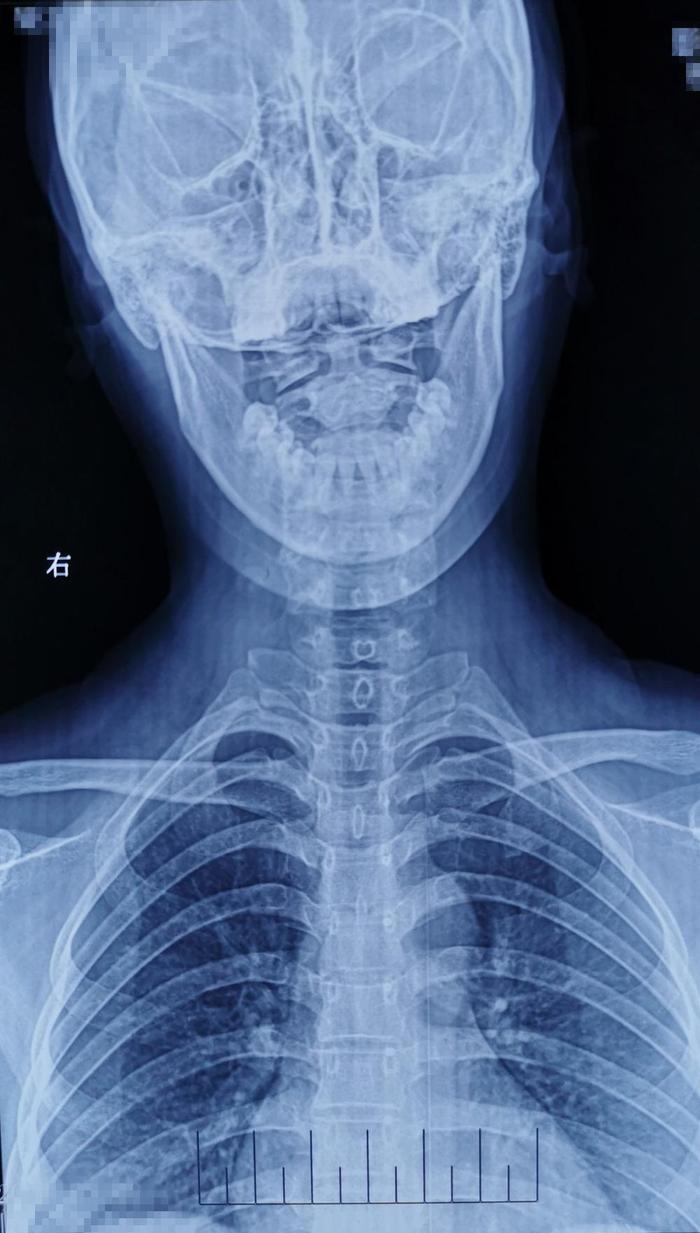

术前影像学资料: